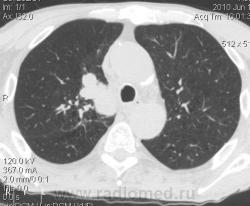

Мужчина 69 лет, с последствием ОНМК находился в доме-интернате для инвалидов. В анамнезе пневмония справа и исходом в пневмосклероз. ФЛГ не проходил 1.5 года. Анализы: СОЭ 20 мм/ч, остальное - без особенностей. Поступил в неврологическое отделение с диагнозом: повторное ОНМК. Невролог заподозрил метастазы головного мозга, направил на рентгенографию легких. После выявленых изменений в правом легком, пациент направлен на КТ головного мозга и грудной полости. От контрастирования и бронхоскопии категорически отказался.

По поводу подозрения на туберкулез пациента в прошлом нодократно проверяли, исключили. ФЛГ архива у меня нет. Все только со слов пациента. Кальцинаты в корне массивные. Трудно сказать, откуда опухоль (если это не конгломерат лимфоузлов!) плотностью 35 ед.Н - то ли из вехнедолевого бронха, который имеет культю 0.4 см и заканчивается выпуклым контуром, но при этом сохраняется воздушность почти всей доли; то ли периферический с центром в прикорневой зоне и вторичным прорастанием ВДБ. К сожалению забыла про снимок легких, на днях выставлю. Я первоначально считала периферический (верхушка, на фоне пневмосклероза) с мтс средостения. По плотности на верхушке узелок 5 ед.Н, только поэтому засомневалась, где же первичный. Лимфоузлы средостения множественные, до 2 см. Кроме того, на верхней стенке правого главного бронха есть мелкое образование такой же 35 е.Н плотности, то ли аденома, то ли прорастает... Без бронхоскопии - только гадать

это периферический рак S2 в/доли правого легкого с мтс во внутригрудные л/узлы.

А тут нечего гадать - данную демонстрацию можно поместить в учебник: узловое образование, с бугристыми, лучистыми контурами, связаное с плеврой, "дорожкой" к корню, перифокальной инфильтрацией. Корень расширен полицикличен за счет конгломерата увеличеных бронхопульмональных, трахеобронхиальных и бифуркационных л/узлов, значительно сдавливающих в/долевой бронх, с нарушением вентиляции в/доли.

Центральный рак ВДБ справа с мтс в л/узлы паратрахеальные нижние, верхние справа, БФ. МТС в головной мозг. А про печень мало сканов

Мне кажется в 6 сегменте печени мтс + еще мтс поражение левого надпочечника вероятнее всего. Мтс в нижние паратрахеальные (с обеих сторон)+бифуркационные л/у. Поражения верхних паратрахеальных не вижу (на коронарах), аксиалы - не показыны сканы выше верхнего края дуги аорты, так что я бы не говорил про поражение верхних медиастинальных лимфоузлов (хотя тут это уже не принципиально) + мтс в головной мозг. А так - центральный рак правого легкого.